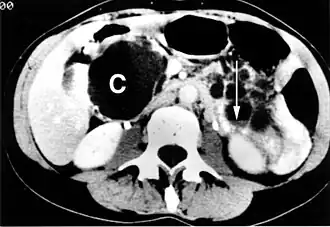

![]() Un gran quiste pancreático en el proceso unciforme del páncreas | ||